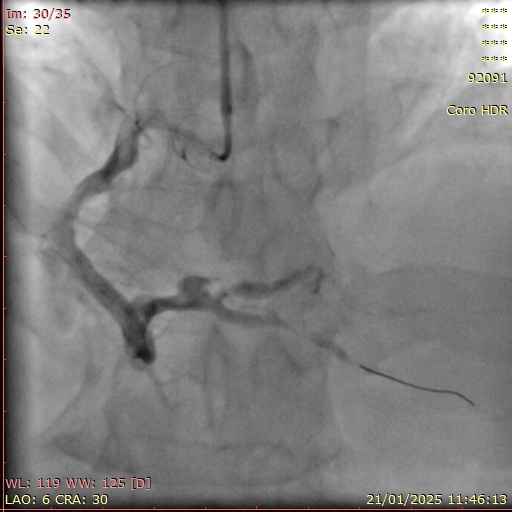

Diagnostic coronary angiography was performed via right radial access using a 5F TIG diagnostic catheter:LM: short, no stenosisLAD: large calibre from ostial to mid LAD with intermediate stenosis at mid LAD, TIMI 3 flowLCx: non-dominant, large calibre, no stenosis, TIMI 3 flowRCA: dominant, very large calibre, diffuse ectasia, TIMI 2 flow with haziness suggestive of thrombus from distal RCA extending to PLB & PDA

Index procedure:Right radial access with SAL 0.75/6F guide and 6F guide extension catheter. Wiring succeeded with Fielder XTR. Sequential predilation with 2.5/15 mm SC balloon, followed with aspiration thrombectomy & intracoronary injections of tirofiban & fasudil via the thrombectomy catheter. Evaluation angiography showed residual large thrombus burden. IVUS catheter had a significant bias due to the large vessel calibre, it could only reach as far as distal RCA. IVUS revealed heavy burden of consolidated thrombus in distal RCA with diffuse ectasia. Predilation with 3.0/15 mm NC balloon and further intracoronary injections of tirofiban via guide catheter still produced a significant residual thrombus burden, albeit with a slightly better distal flow. Deferred stenting and put the patient on anticoagulant on top of DAPT.